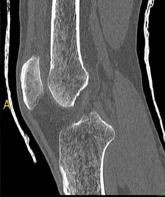

Bei dieser Untersuchung ist keine spezielle Vorbereitung notwendig. Meist werden Sie Kontrastmittel intravenös verabreicht bekommen. Bei der Darstellung der Speiseröhre müssen Sie vor der Untersuchung auf dem Untersuchungstisch einen Becher Kontrastmittel trinken.

Die Untersuchungsdauer beträgt ca. 10 Minuten.